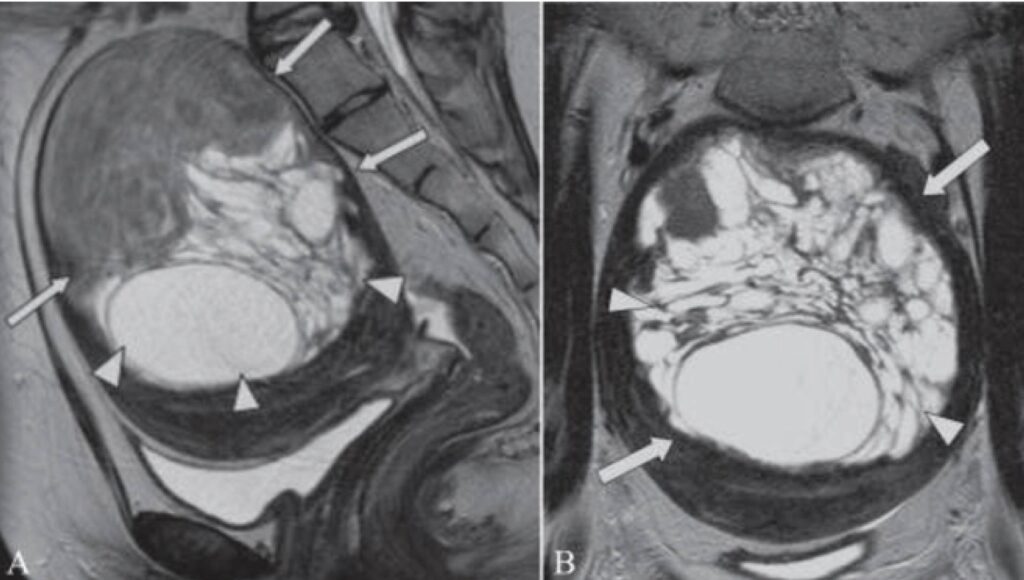

- Siêu âm ổ bụng, siêu âm đầu dò để kiểm tra tử cung, buồng trứng.

- Nội soi tử cung giúp phát hiện tổn thương niêm mạc, polyp hoặc u xơ.

Sau khi đến Đông Đô IVF Center, chị được bác sĩ Cương trực tiếp thăm khám, siêu âm phát hiện nhiều u xơ nhỏ trong thành tử cung và vùng niêm mạc có dấu hiệu viêm kéo dài. Bác sĩ kết hợp làm xét nghiệm máu, đánh giá hormone sinh dục, kiểm tra chức năng đông máu, xác định thêm chị có rối loạn thiếu nội tiết nhẹ.